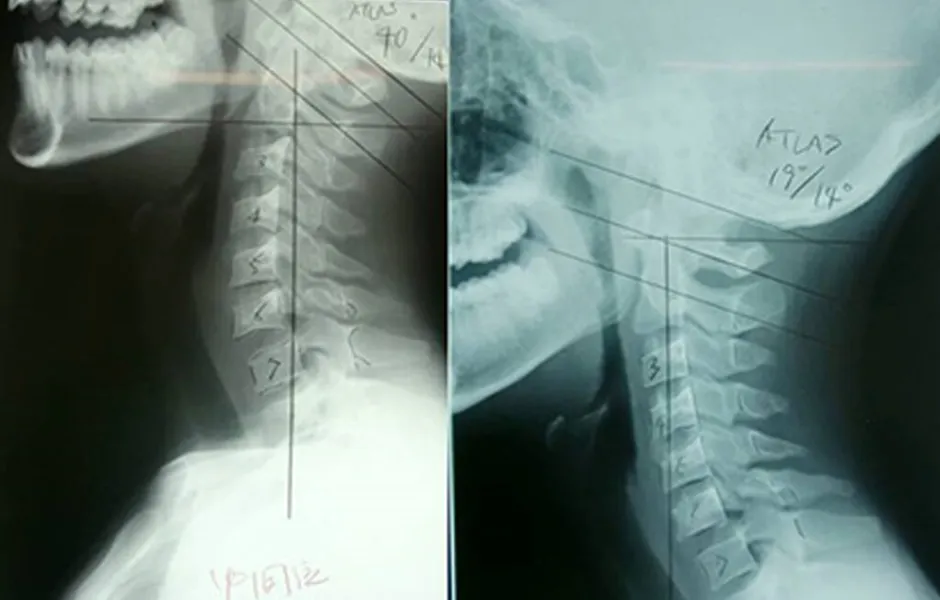

- 当院のアトラスオーソゴナルカイロプラクティックは、より正確なアジャストメントを目指し、水平な第一頚椎(アトラス)に対し垂直な頭と首の関係性にこだわり、脊柱全体をダイナミックに最適化します。

「アトラスを基準とした構造の適正化」で、的確な改善を約束

症状を追って局所的に矯正するのではなく、「第一頚椎(アトラス)に特化したアプローチ」で、頚椎・背骨・腰椎の骨組み全体を構造的に変化させ神経症状を取り除きます。